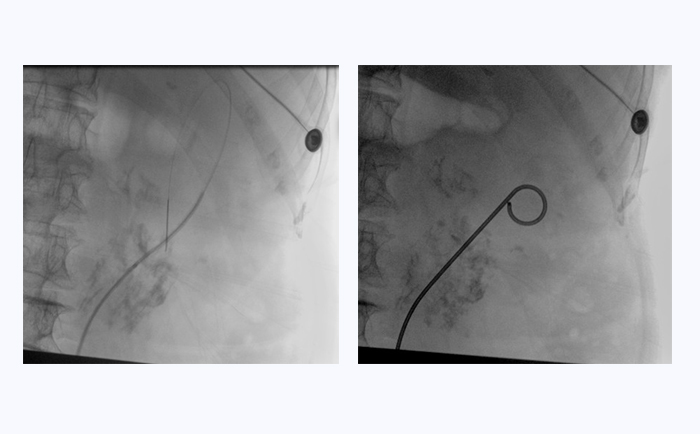

患者采用結石位進行該手術。全麻后,操作輸尿管鏡從尿道進入膀胱,通過鏡下觀察,找到輸尿管開口。此時,在普愛醫療大平板一體式C形臂透視引導下,穿入導絲,到達腎盂并確認位置,同時配合輸尿管鏡,找到狹窄部位。接下來,同樣在透視引導下,沿導絲插入雙J管支架,當支架兩端到達相應位置后,抽出導絲和輸尿管鏡,完成手術。

普愛醫療大平板一體式C形臂臨床圖像